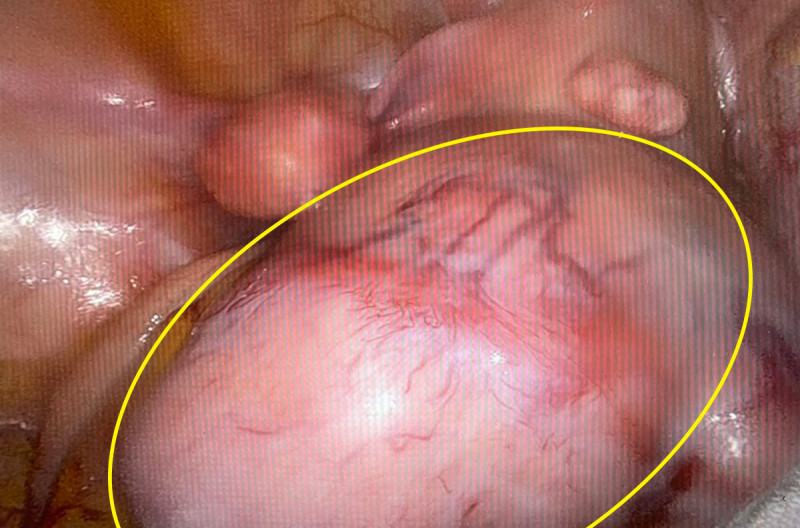

〔記者蔡淑媛/台中報導〕台中一名35歲粉領族即將結婚,擔心罹患多顆子宮肌瘤造成不孕,就醫檢查,發現體內子宮肌瘤又多又大,是年輕型的子宮肌瘤患者,因體質及年紀輕,血中雌激素刺激讓子宮肌瘤快速長大,接受達文西機械手臂手術,由肚臍開刀取出9顆肌 瘤,從1到9公分不等共9顆,最大肌瘤大如拳頭般,但手術沒有明顯傷口,把傷口隱藏在肚臍裡。

患者因工作和婚期考量,接受達文西手臂手術能較快復原。謝昌興指出,手術在肚臍劃開一個3公分傷口,手臂進入腹腔,切除肌瘤,縫合傷口,再將過大肌瘤切割成小塊,從肚臍小傷口取出,接著縫合肚臍小傷口,術後看不出有傷口,住院3天出院就能上班工作。